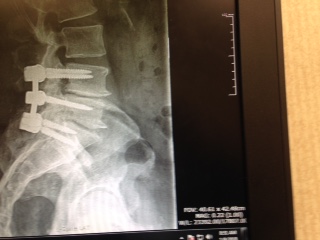

Over the next six months I had further tests done at HSS, Dr. Goodwin consulted with a neurologist, Dr. Reichler, and I researched the doctor and the hospital. After two more appointments, Dr. Goodwin told me that the only good approach to easing my pain was to perform a laminectomy and instrumented fusion on my L4, L5, and S1 vertebrae. I agreed to the procedure and on the morning of December 15th I entered the hospital. Thus began an experience I can only describe as amazing.